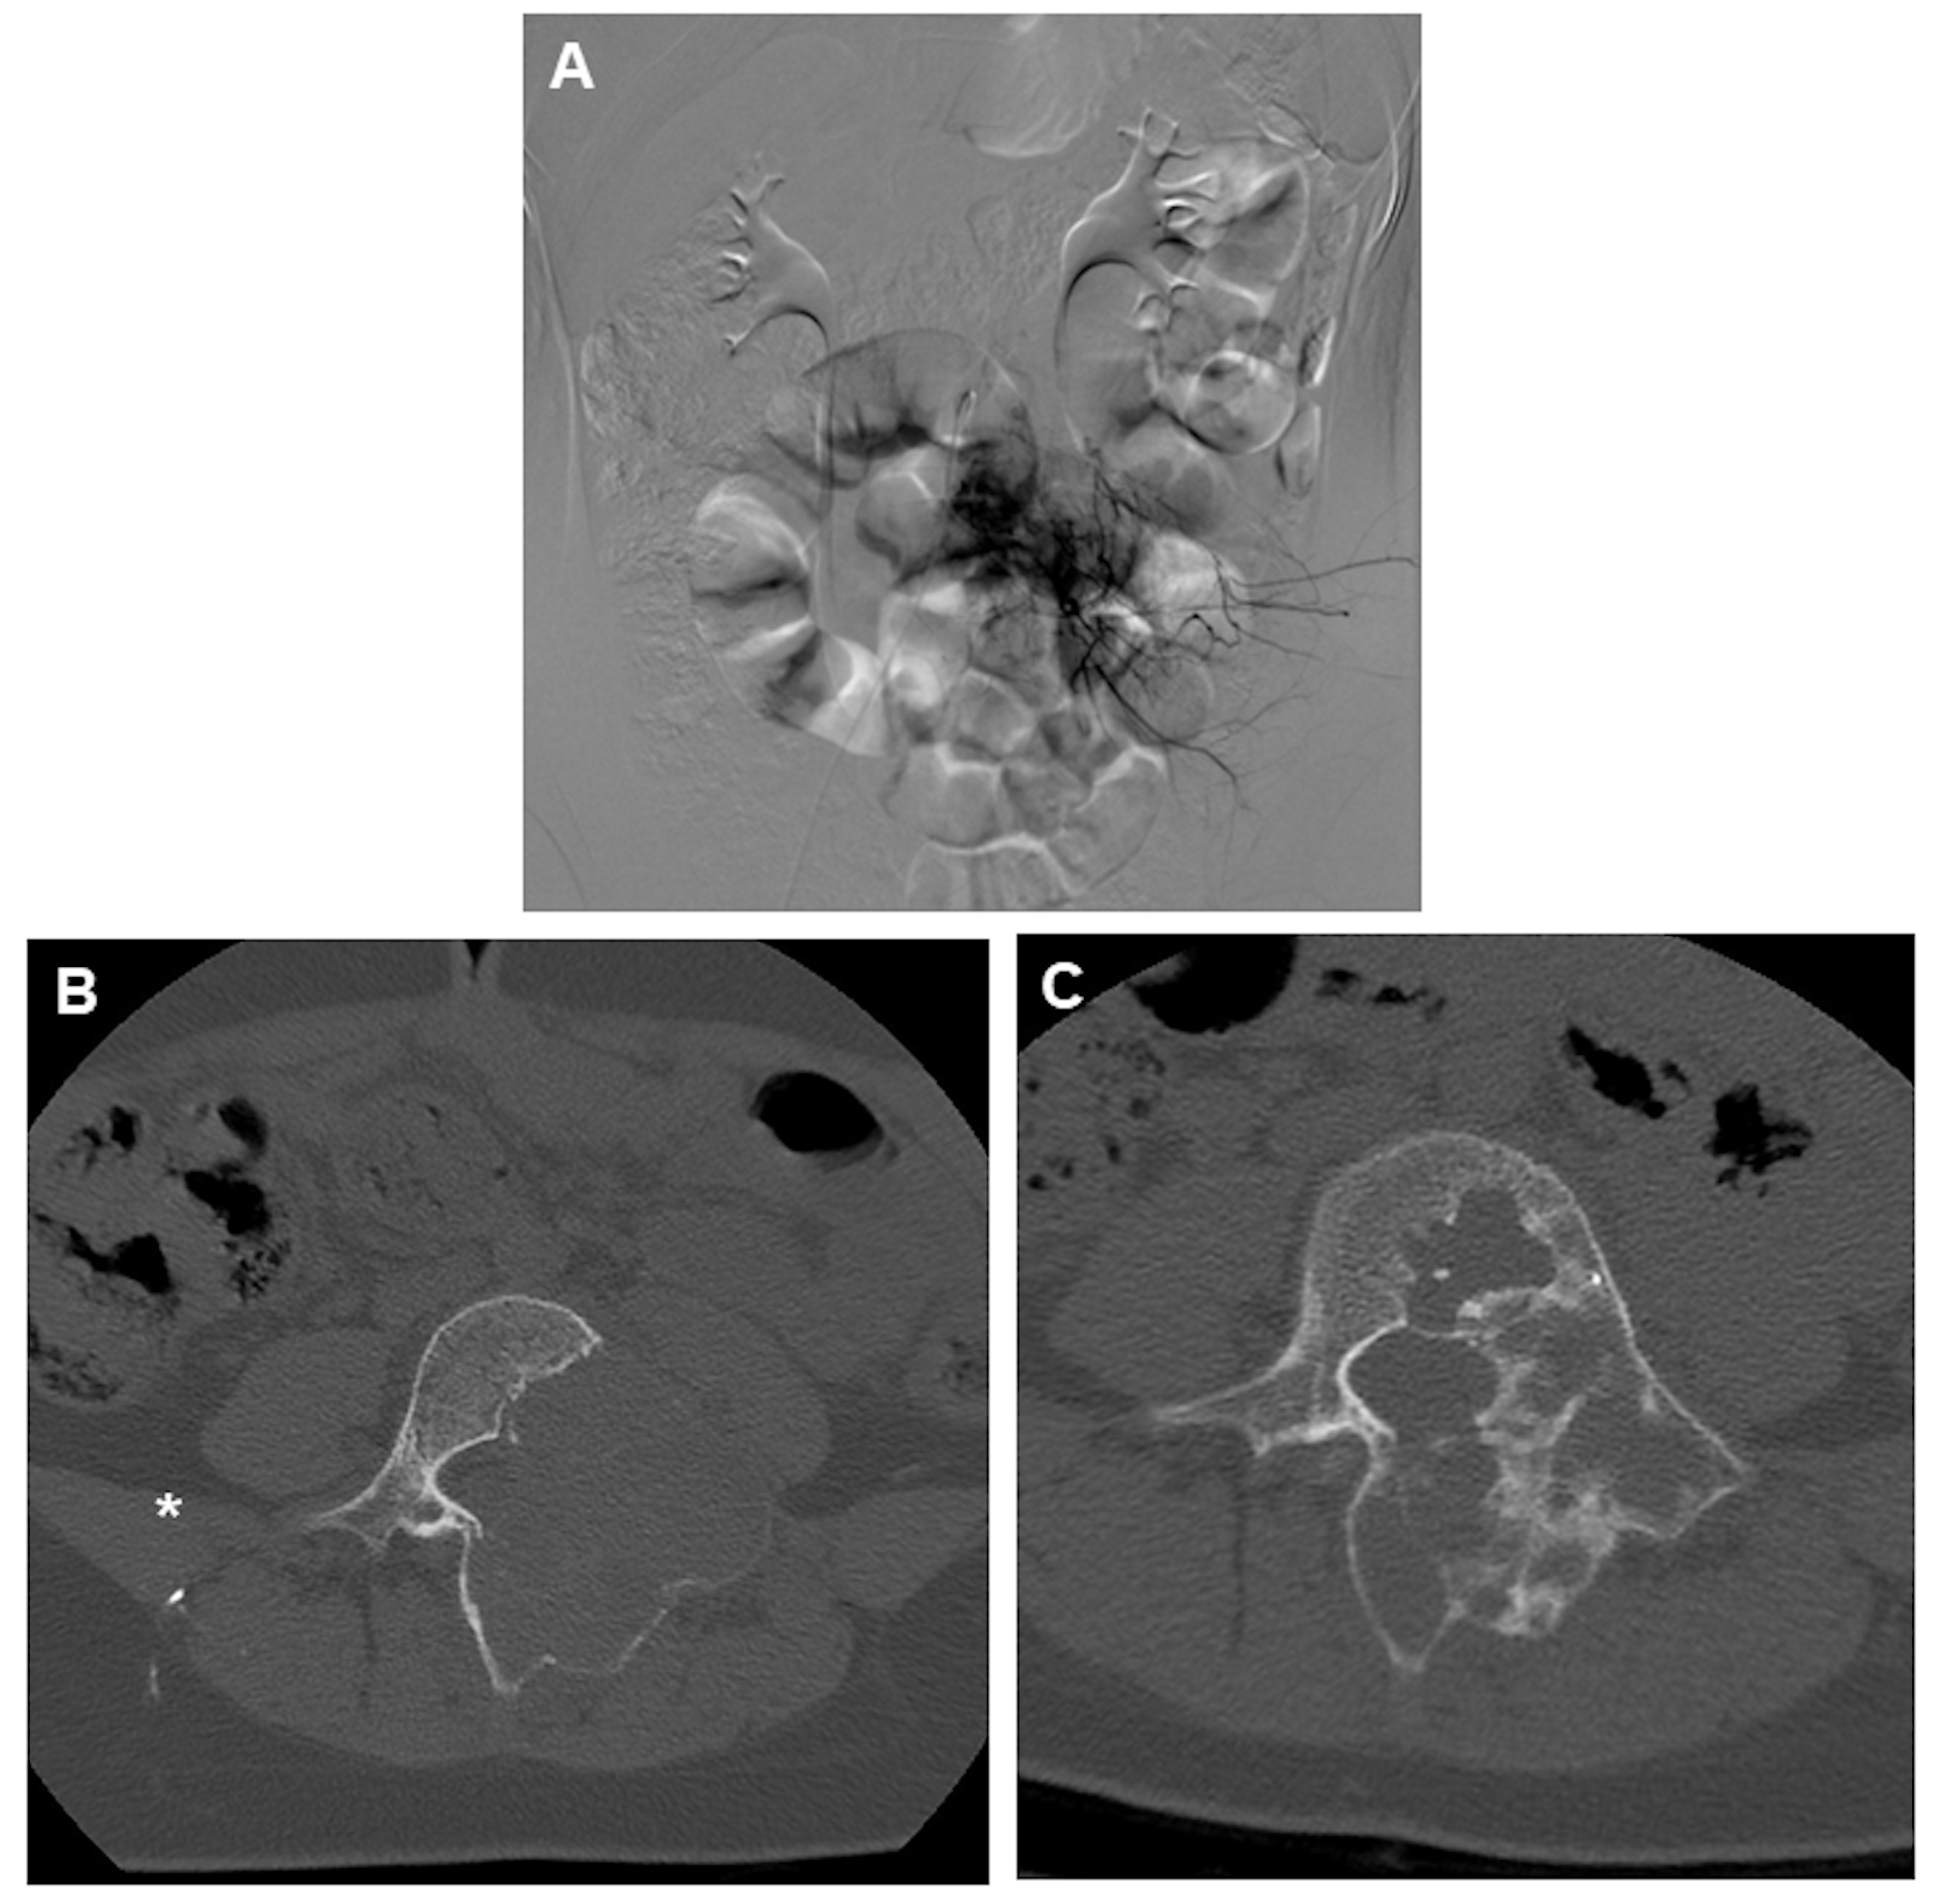

2.5.2. Aneurysmal Bone Cysts

2.6. Treatment Through Embolization